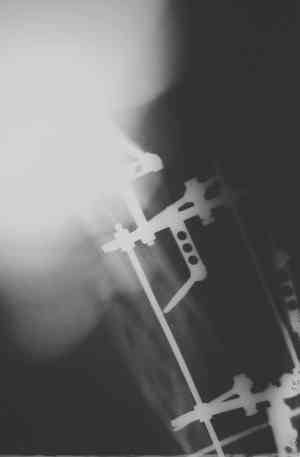

Уважаемые коллеги! Пришел на консультацию вот такой больной (первые 3-и рисунка). Травма автодорожная, апрель 2006г. Лечился консервативно, вытяжение и гипс. Через пять месяцев стал ходить. Укорочение бедра 6 см. 26 февраля 2007г. оступился, упал. Прооперирован в г.Баку - наложен стержневой аппарат. Ходит с костылями, наступая на левую ногу. Мы попросили что нибудь из ранних снимков. Принес рентгенограммы перелома (рис. 4,5). Посмотрели, наснимали сами (рис. 6-10). Похоже, что нет сращения нигде. Хотелось - бы обсудить следующие вопросы:1. дальнейшая тактика - реостеосинтез или подождать (ослабить аппарат, дать нагрузку и т.д.)?2. если реостеосинтез - то чем и как? Юрий Алексеевич Булахтин

Юрий Алексеевич. Привет. А сустав тазобедренный живой? На одном из снимков он возник - но качество рентгенограммы - швах. Если он жживой то я бы сделал

гвоздь с блокированием, через некоторое время после снятия аппрата, вмешиваясь на больших углах малоинвазивно. А если нет.....То стоит подумать

об ТHR с очень длинной ножкой. А Рыков. Хабаровск.